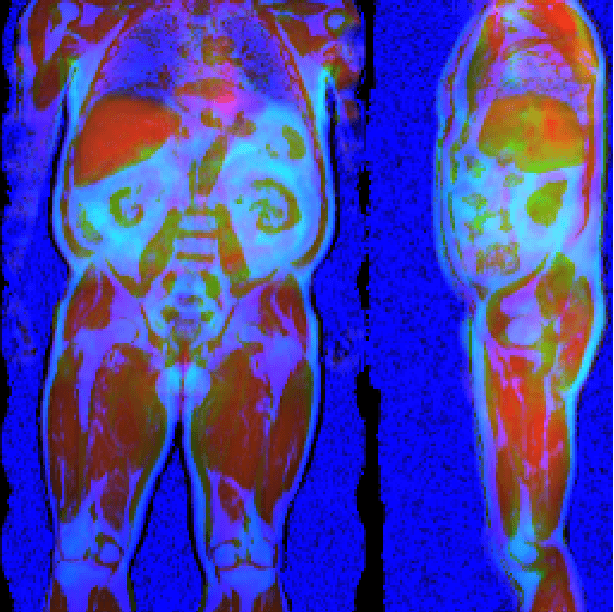

Abstract:Large-scale medical studies such as the UK Biobank examine thousands of volunteer participants with medical imaging techniques. Combined with the vast amount of collected metadata, anatomical information from these images has the potential for medical analyses at unprecedented scale. However, their evaluation often requires manual input and long processing times, limiting the amount of reference values for biomarkers and other measurements available for research. Recent approaches with convolutional neural networks for regression can perform these evaluations automatically. On magnetic resonance imaging (MRI) data of more than 40,000 UK Biobank subjects, these systems can estimate human age, body composition and more. This style of analysis is almost entirely data-driven and no manual intervention or guidance with manually segmented ground truth images is required. The networks often closely emulate the reference method that provided their training data and can reach levels of agreement comparable to the expected variability between established medical gold standard techniques. The risk of silent failure can be individually quantified by predictive uncertainty obtained from a mean-variance criterion and ensembling. Saliency analysis furthermore enables an interpretation of the underlying relevant image features and showed that the networks learned to correctly target specific organs, limbs, and regions of interest.

Abstract:Purpose: To enable fast and automated analysis of body composition from UK Biobank MRI with accurate estimates of individual measurement errors. Methods: In an ongoing large-scale imaging study the UK Biobank has acquired MRI of over 40,000 men and women aged 44-82. Phenotypes derived from these images, such as body composition, can reveal new links between genetics, cardiovascular disease, and metabolic conditions. In this retrospective study, neural networks were trained to provide six measurements of body composition from UK Biobank neck-to-knee body MRI. A ResNet50 architecture can automatically predict these values by image-based regression, but may also produce erroneous outliers. Predictive uncertainty, which could identify these failure cases, was therefore modeled with a mean-variance loss and ensembling. Its estimates of individual prediction errors were evaluated in cross-validation on over 8,000 subjects, tested on another 1,000 cases, and finally applied for inference. Results: Relative measurement errors below 5\% were achieved on all but one target, for intra-class correlation coefficients (ICC) above 0.97 both in validation and testing. Both mean-variance loss and ensembling yielded improvements and provided uncertainty estimates that highlighted some of the worst outlier predictions. Combined, they reached the highest quality, but also exhibited a consistent bias towards high uncertainty in heavyweight subjects. Conclusion: Mean-variance regression and ensembling provided complementary benefits for automated body composition measurements from UK Biobank MRI, reaching high speed and accuracy. These values were inferred for the entire cohort, with uncertainty estimates that can approximate the measurement errors and identify some of the worst outliers automatically.